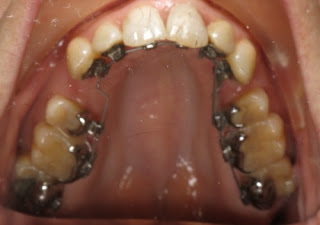

Time for a quick update - it's been almost 2 months since my last post and not really much progress unfortunately. I'm posting updated pics, where you can see that the bottom teeth are straightening out a little bit but the gap at the top really hasn't closed at all. I've been very frustrated and after discussing it with Dr. Cliff I'm going to get the bottom braces taken off and replaced with self-ligating outside braces. This is because I've broken yet another wire on the bottom, and I'm sick of my tongue being constantly cut up and sore. I think it will be less of a transition on the bottom (switch sore tongue for sore inner lip for awhile) and because hopefully I won't break the wires on top. I doubt that I will switch the uppers, even though he thinks it will reduce the total treatment time by about 3 months, just because I still don't want to deal with food stuck in my braces while at company lunches/dinners, and because the top ones don't bother me all that much - I just wish they would hurry up and straighten!!! We moved up to a new wire on the top so hopefully that will help things move along, although I'll feel better when we put the power threads back on to close the gap on the left.

Here are the latest pics from July, unfortunately a couple of the pics have weird marks on them, it looks like there was hair on the camera lens or something but you get the idea: